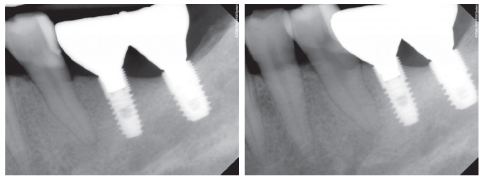

Figure 3

Periapical view taken 2 years ago.

Figure 3 Periapical view taken 2 years ago.